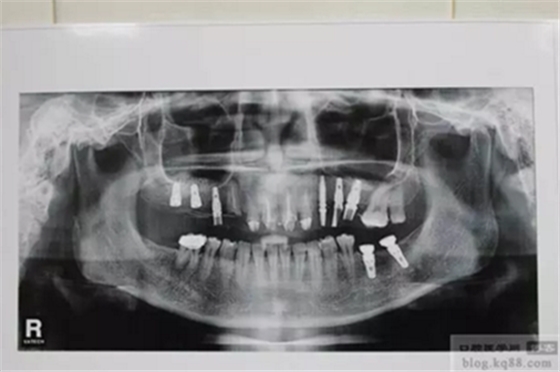

上前牙做充填和纖維樁修復后左上后牙內(nèi)提升植入三顆植體

右上后牙外提升

直接上基臺做臨時樹脂橋體,即刻負重

上圖為術(shù)后1年X光片 上基臺